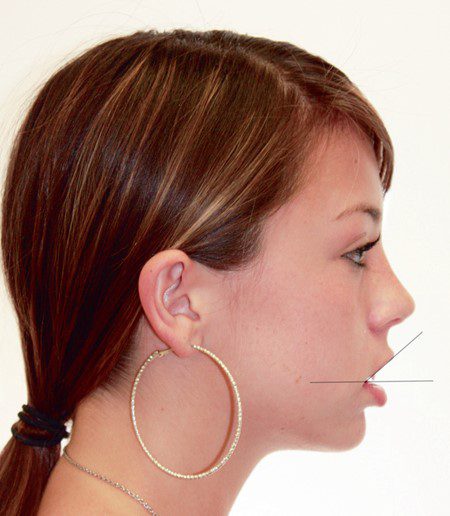

Từ góc nhìn nghiêng, một dấu hiệu chung của môi trên ngắn là góc tù được tạo thành giữa đường nối từ khoé miệng đến điểm labrale superioris (điểm giữa viền môi trên) và mặt phẳng tham chiếu nằm ngang (hình 1-23).

Nói chung, môi dưới gần như song song với mặt phẳng ngang; do đó, những bệnh nhân này sẽ có khoảng hở giữa hai môi quá mức.

Một cấu trúc quan trọng khác cũng được đánh giá ở góc nhìn bên là sự nhô của cằm. Ở bệnh nhân trưởng thành, tỷ lệ giữa chiều dài từ cằm đến cổ họng so với chiều cao phần dưới của khuôn mặt là 1,2 : 1,8. Có vẻ như không chỉ chiều dài của đường này mà cả góc nghiêng của nó so với mặt phẳng ngang thực sự cũng là những yếu tố quan trọng góp phần làm khuôn mặt hài hòa.

Thông thường, tương quan song song hoặc có góc âm nhẹ (điểm cổ họng nằm cao hơn điểm menton) được thấy ở những khuôn mặt có thẩm mỹ tốt (hình 1-27A). Cằm kém phát triển sẽ thể hiện qua sự giảm chiều dài từ cằm đến cổ họng (hình 1-27B).